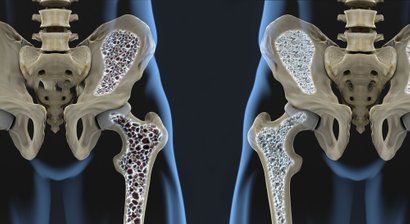

Labrumläsion der Hüfte – Diagnose und Therapie

Behandlung von Knorpelschäden an der Hüfte

Implantation eines künstlichen Hüftgelenks (Hüfttotalendoprothese)